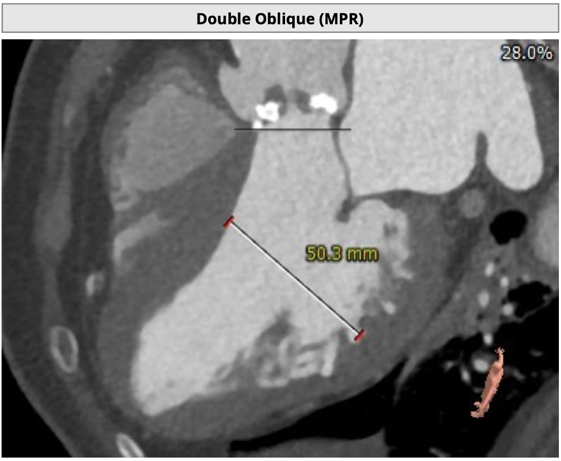

左冠开口高度8.6mm,右冠开口高度15.0mm,左冠高度偏低,左冠瓣瓣尖钙化明显,根据瓦氏窦内径和瓣叶长度综合判断,左冠存在较高堵塞风险;左心室后壁增厚。